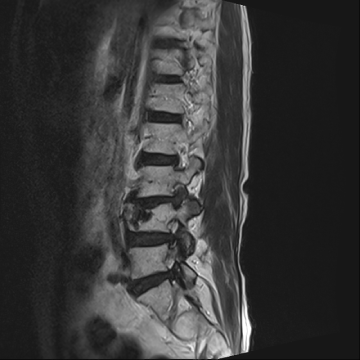

허리 디스크 수술 전·후

2021.10.19

2023.01.09

ㆍ환자 동의를 받은 자료이며, 이미지 사진은 실물과 다를 수 있습니다.

ㆍ모든 자료는 새움병원 자료입니다.